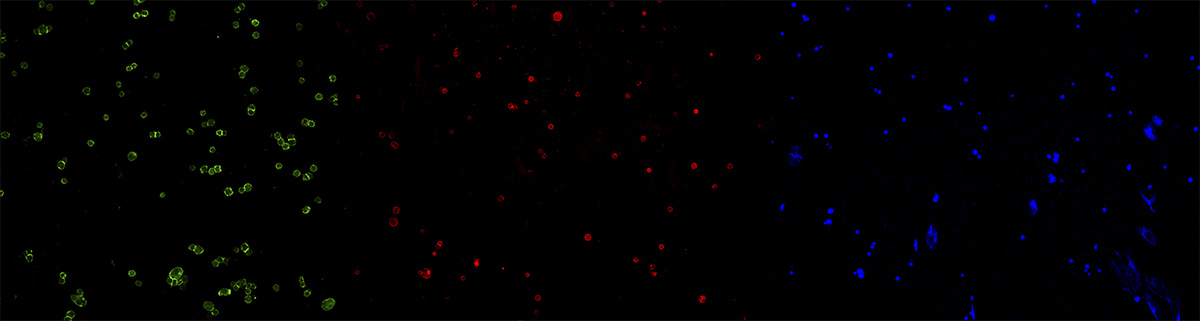

多通道荧光图像